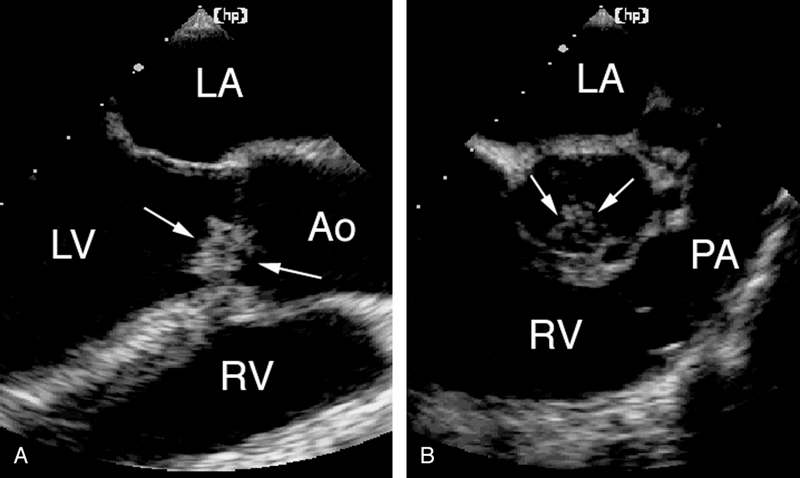

فحوصات تشخيصية لبعض امراض القلب والشرايين التاجية